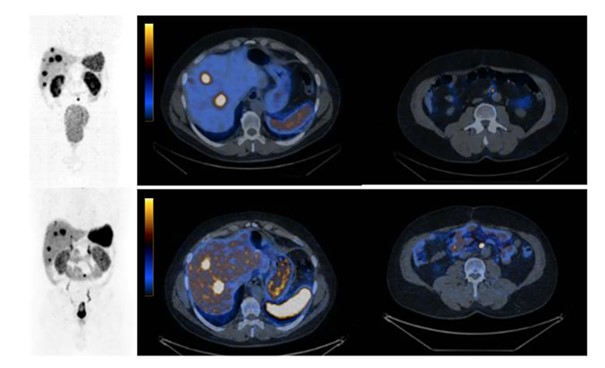

Comparison of SPECT/CT imaging using a new radiopharmaceutical, the SSTR antagonist, [99mTc]Tc-TECANT1 (top panel), with PET/CT imaging using the agonist [68Ga]Ga-DOTA-TATE (bottom panel). It should be noted that there was a more pronounced accumulation of [99mTc]Tc-TECANT1 in lesions (6 out of 7 lesions were visualized) as well as a significantly higher ratio of accumulation in the lesions in relation to the background compared to the PET/CT examination with [68Ga]Ga-DOTA-TATE.

For the first time, the results of SPECT/CT imaging after administration of the investigated radiopharmaceutical 99mTc[Tc]-TECANT-1 in a patient with neuroendocrine tumor were shown in the publication: Opalinska, M., Lezaic, L., Decristoforo, C. et al.: “Comparison of 99mTc radiolabeled somatostatin antagonist with [68 Ga]Ga-DOTA-TATE in a patient with advanced neuroendocrine tumor”, Eur J Nucl Med Mol Imaging 50, 4110–4111 (2023), https://doi.org/10.1007/s00259-023-06335-9.